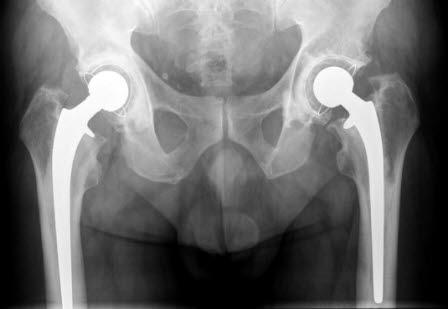

En total hofteprotese innebærer at både lårbeinshodet og hofteskåla skiftes ut med kunstige deler. Et alternativ er at bare lårbeinshodet erstattes med protese som vist på bildet, det kalles en halvprotese.

Hofteoperasjonen består i å erstatte lårbeinshodet med et metallhode (halvprotese) eller i tillegg også skifte ut hofteskålen (totalprotese). Metallhodet er støpt sammen med et metallskaft som passer inn i lårbeinet ditt. En plast- og metallskål festes til hoftebeinet (pelvis) og erstatter eventuelt den ødelagte hofteskålen. Protesedelene, som er svært like de beindelene som erstattes, passer sammen og vil fungere som et normalt hofteledd.